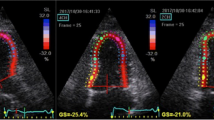

Color tissue Doppler strain images assessing LA function were obtained from the apical four-chamber view and recorded at >110 frames/s. The narrowest image sector angle (usually 30°) was used for the maximum color Doppler frame rate, and the atrial wall was aligned parallel to the Doppler beam. The sample volume was placed in the basal segments of the septal and lateral LA walls in the apical four-chamber view. The peak systolic strain of the lateral and septal LA walls during late LV systole was measured during the conduit phase corresponding to LA diastasis (Fig. 1a) [27]. The strain rate (Sr) of the LA septal and lateral walls was measured in LV systole (S-Sr), early diastole (E-Sr), as well as late LV diastole (A-Sr). S-Sr was considered an index of LA reservoir function, while E-SR and A-SR were indices of LA conduit function and LA contractile function, respectively (Fig. 1b) [28]. Three cine loops were recorded for each patient and saved digitally on an optical disk for later analysis. Offline measurements were performed using a dedicated software package (Echo PAC PC; GE Healthcare, Waukesha, WI, USA). All echocardiographic measurements were calculated as averages from three beats.

Two examples of tissue Doppler imaging recordings. a Left atrial (LA) strain curve recorded within the LA wall. The peak systolic strain (Peak S) was measured. b LA strain rate (SR) curve recorded within the lateral LA wall. SR was measured during left ventricular (LV) systole (S-SR), early diastole (E-SR), and late LV diastole (A-SR)